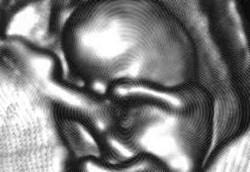

Bayi Sehat Lahir dari Embrio yang Dibekukan 20 Tahun

Melestarikan embrio dengan pembekuan telah menjadi umum dalam perawatan kesuburan yang memungkinkan perempuan dengan gangguan kesuburan memiliki anak. Dan seorang bayi sehat telah lahir dari embrio yang dibekukan sejak 20 tahun lalu.